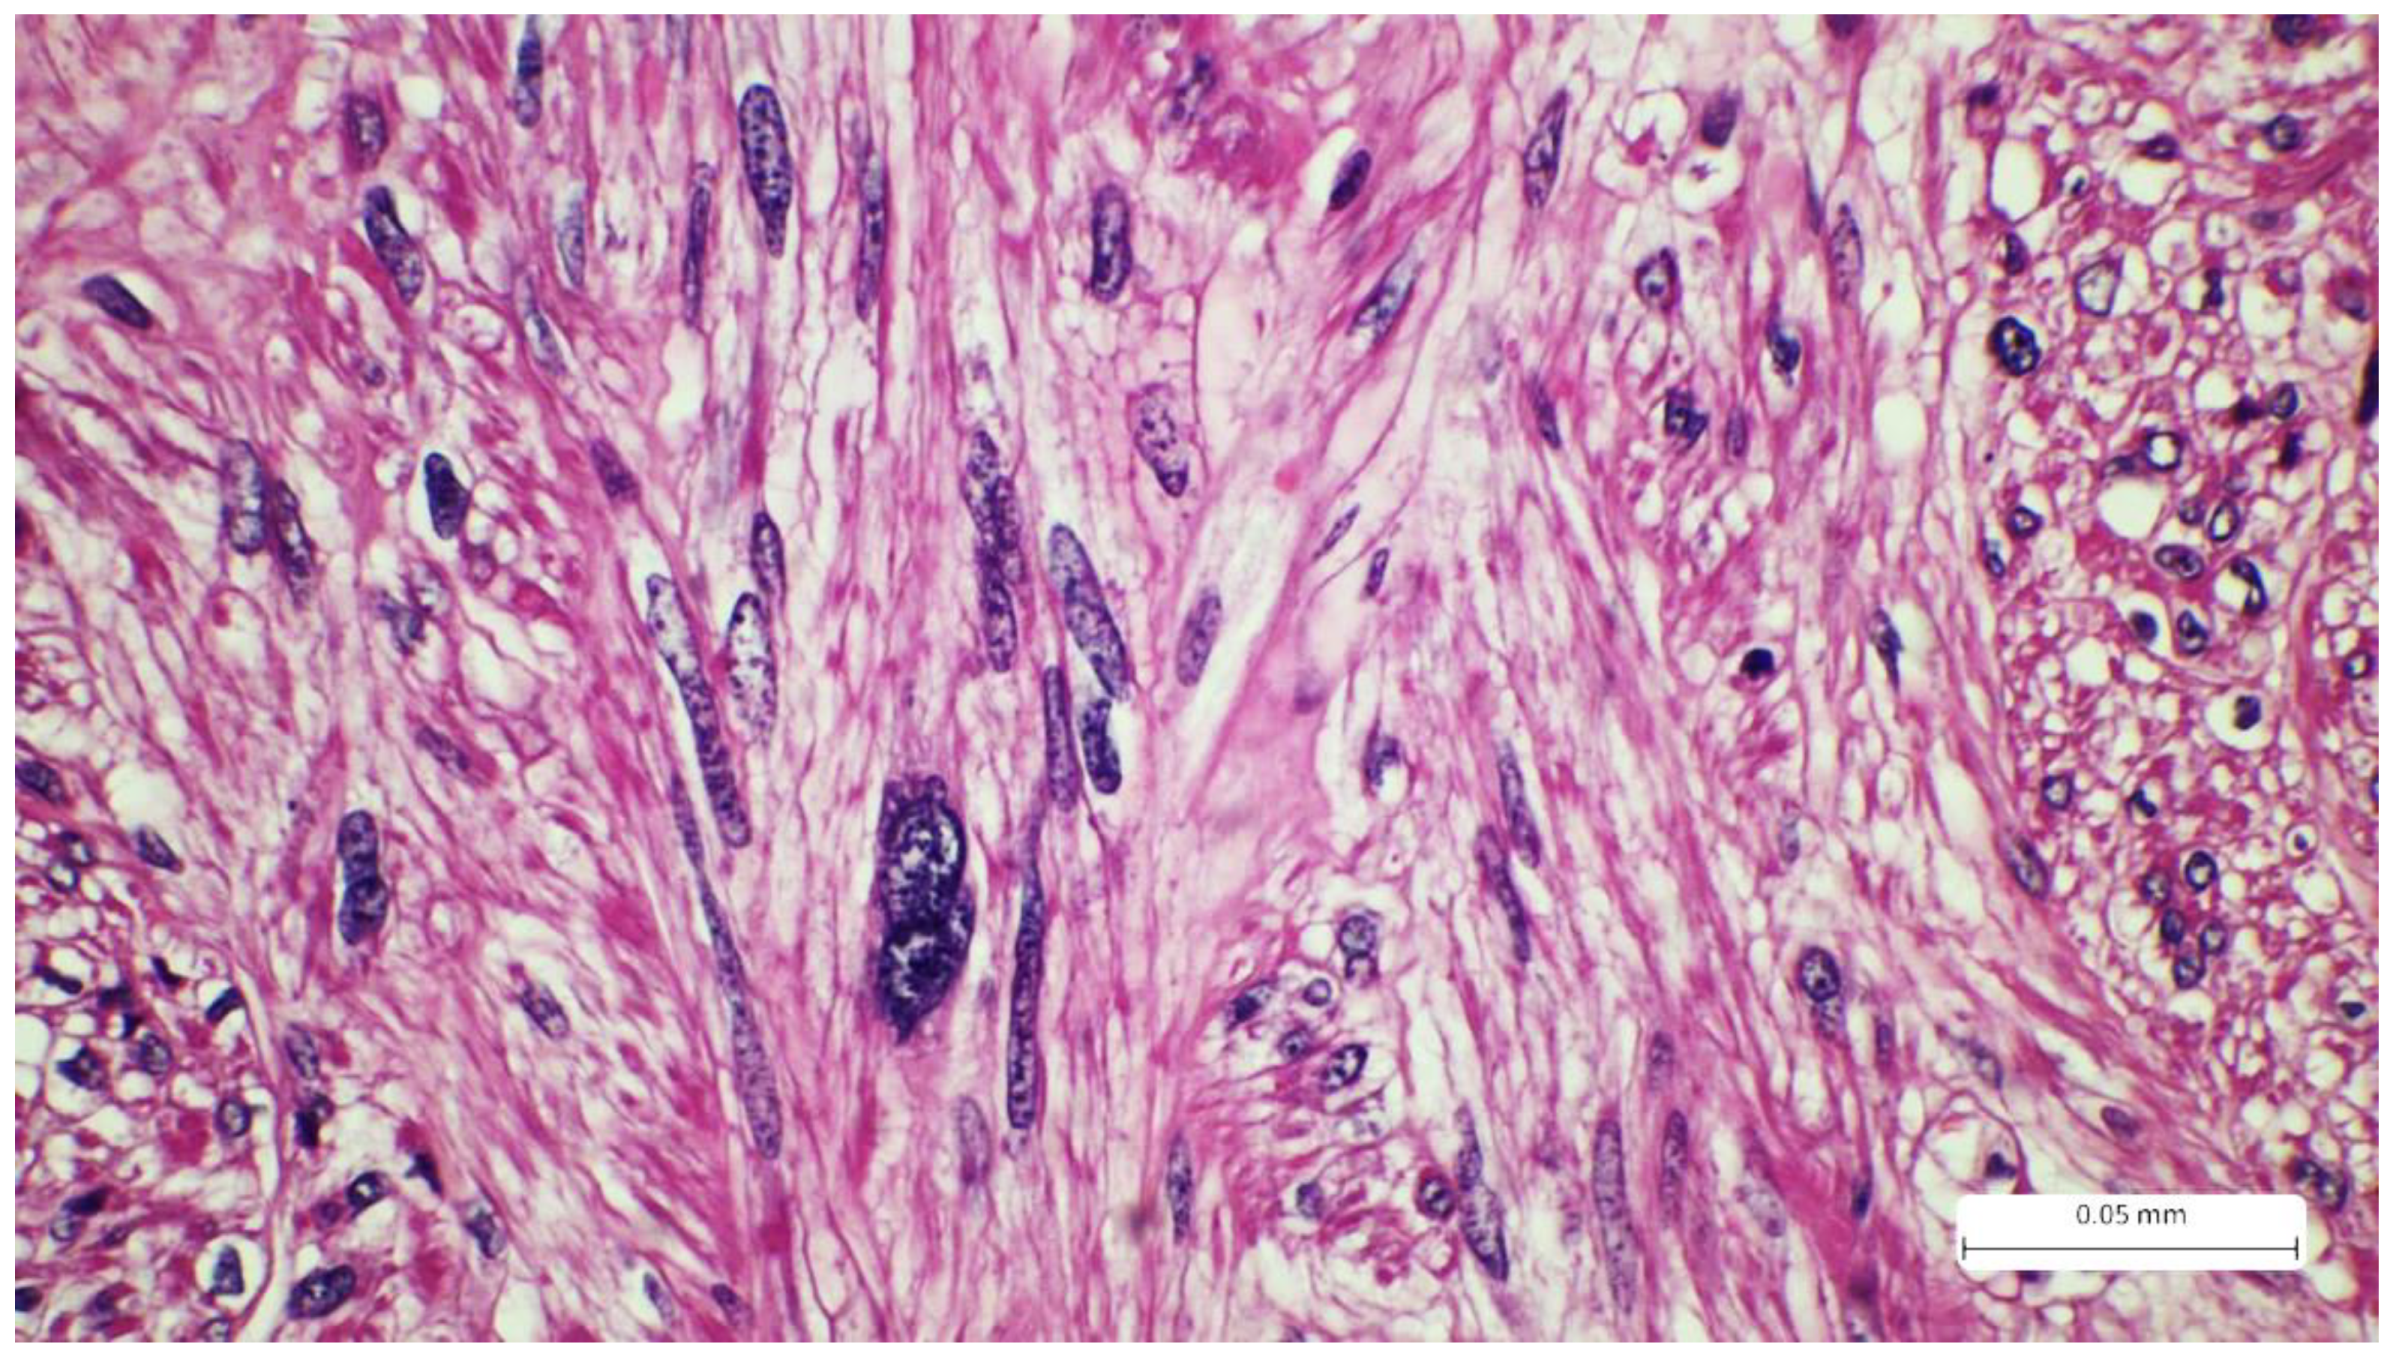

Recurrent Cutaneous Leiomyosarcoma: A Histopathological Perspective and the Quest for Complete Excision

2. Case Report